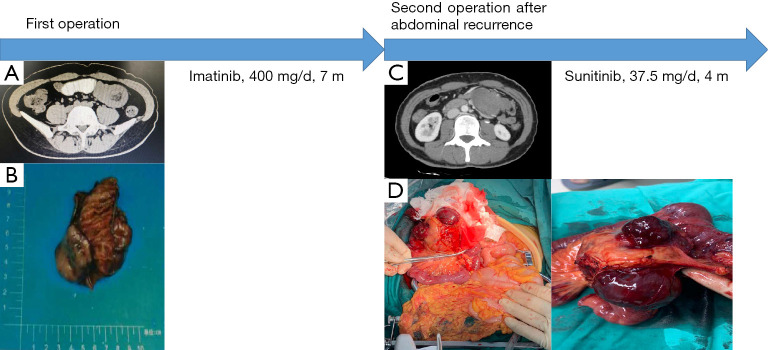

圖 2

案例第 2 階段的圖形摘要。 (A) 無法識別的肝臟微觀病變(由紅色圓圈顯示)。 (B) 腹主動脈旁的小淋巴結(jié)(紅色圓圈所示)。 (C) 少量盆腔積液。 (D) 肝轉(zhuǎn)移。 (E) 主動脈旁轉(zhuǎn)移。 (F) 盆腔腹水和轉(zhuǎn)移性結(jié)節(jié)。

鑒于腫瘤對伊馬替尼有耐藥性,患者在手術(shù)后口服舒尼替尼(37.5 毫克/天)。 患者狀態(tài)良好,未發(fā)生藥物不良反應(yīng)。 2021 年 1 月的腹部 CT 掃描未見明顯異常。 2021年5月腹部磁共振復(fù)查示肝右前葉異常信號,較2021年1月結(jié)果新,考慮血管瘤可能性大(見圖2A)。 此外,在腹主動脈左側(cè)觀察到淋巴結(jié)腫大(見圖 2B),還有少量盆腔積液(見圖 2C)。

患者2021年8月的腹部CT顯示腹部和骨盆多處軟組織結(jié)節(jié)和腫塊,與2021年5月的結(jié)果相比是新的,考慮轉(zhuǎn)移。 腫瘤基因解碼醫(yī)師還注意到肝臟右前葉的低密度病灶比以前更大,并考慮轉(zhuǎn)移(見圖2D)。 此外,在腹主動脈周圍觀察到多個腫大的淋巴結(jié),并考慮轉(zhuǎn)移(見圖2E),并且還觀察到腹部盆腔積液(見圖2F)。 鑒于患者腫瘤的基因突變類型,患者從三線 TKI 瑞戈非尼中獲益的可能性很小,因此患者接受了口服利培替尼(150 mg/天)治療。 2021年10月,患者繼續(xù)服藥,狀態(tài)良好但有輕微腹脹。 她將如期接受審查。